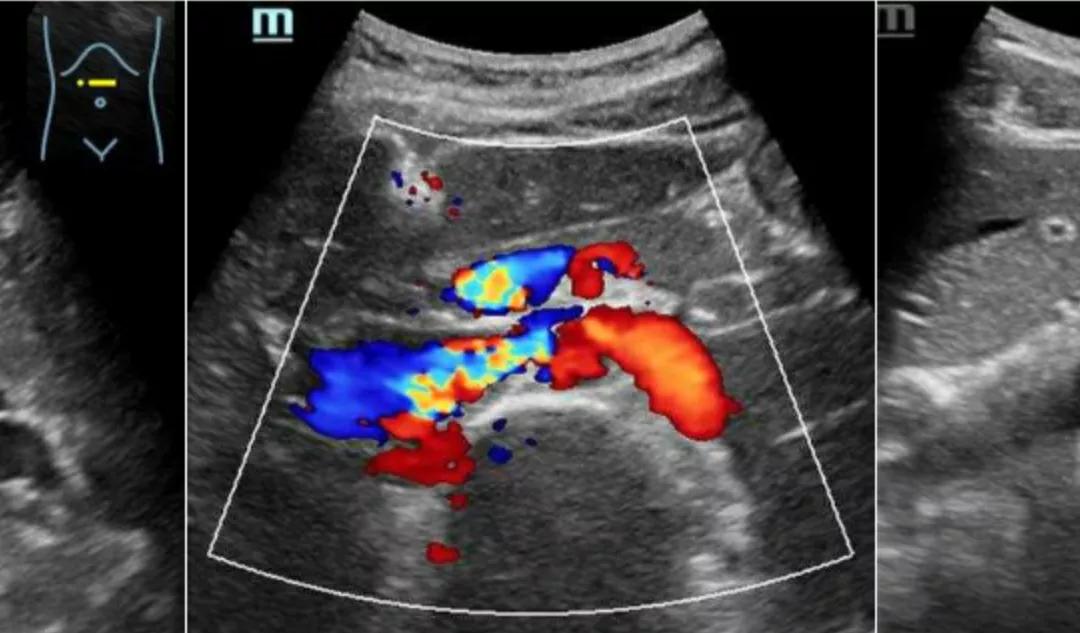

胡桃夹的超声影像图

人体腹主动脉就像一根树枝一样,在腹部分出一条分支,叫肠系膜上动脉,这样子,腹主动脉与肠系膜上动脉就形成了一个夹角,而左肾静脉刚好从这个夹角通过。腹主动脉和肠系膜上动脉就像胡桃夹的两个手把一样,左肾静脉就有如那个胡桃。

正常人这个夹角在40度~60度间,夹角里除了左肾静脉,期间还充以肠系膜、脂肪、淋巴结及腹膜等支撑着,所以走行于此期间的左肾静脉不至于受压。

当这个角度小15度时,穿过这个夹角的左肾静脉就有受压的可能了,从而导至左肾静脉回流受阻,静脉压增高,静脉中的红细胞渗出增多,而出现镜下血尿或肉眼血尿, 同时由于左肾静脉瘀积充血,造成右腰胀痛感觉。